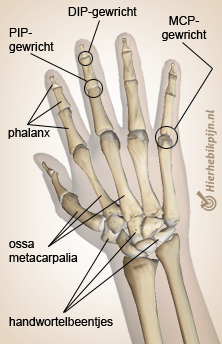

Hand en vingers